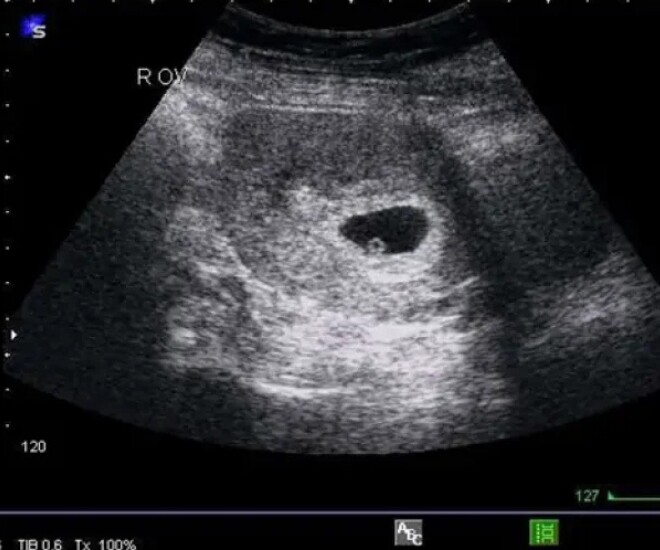

Tuy nhiên, kết quả siêu âm mà bệnh nhân nhận được lại ghi rõ: “Thai sớm trong tử cung, không loại trừ khả năng thai ngừng phát triển”. Nội dung này nhanh chóng gây sốc bởi rõ ràng không thể xảy ra với một bệnh nhân nam cao tuổi.

Ảnh minh hoạ.